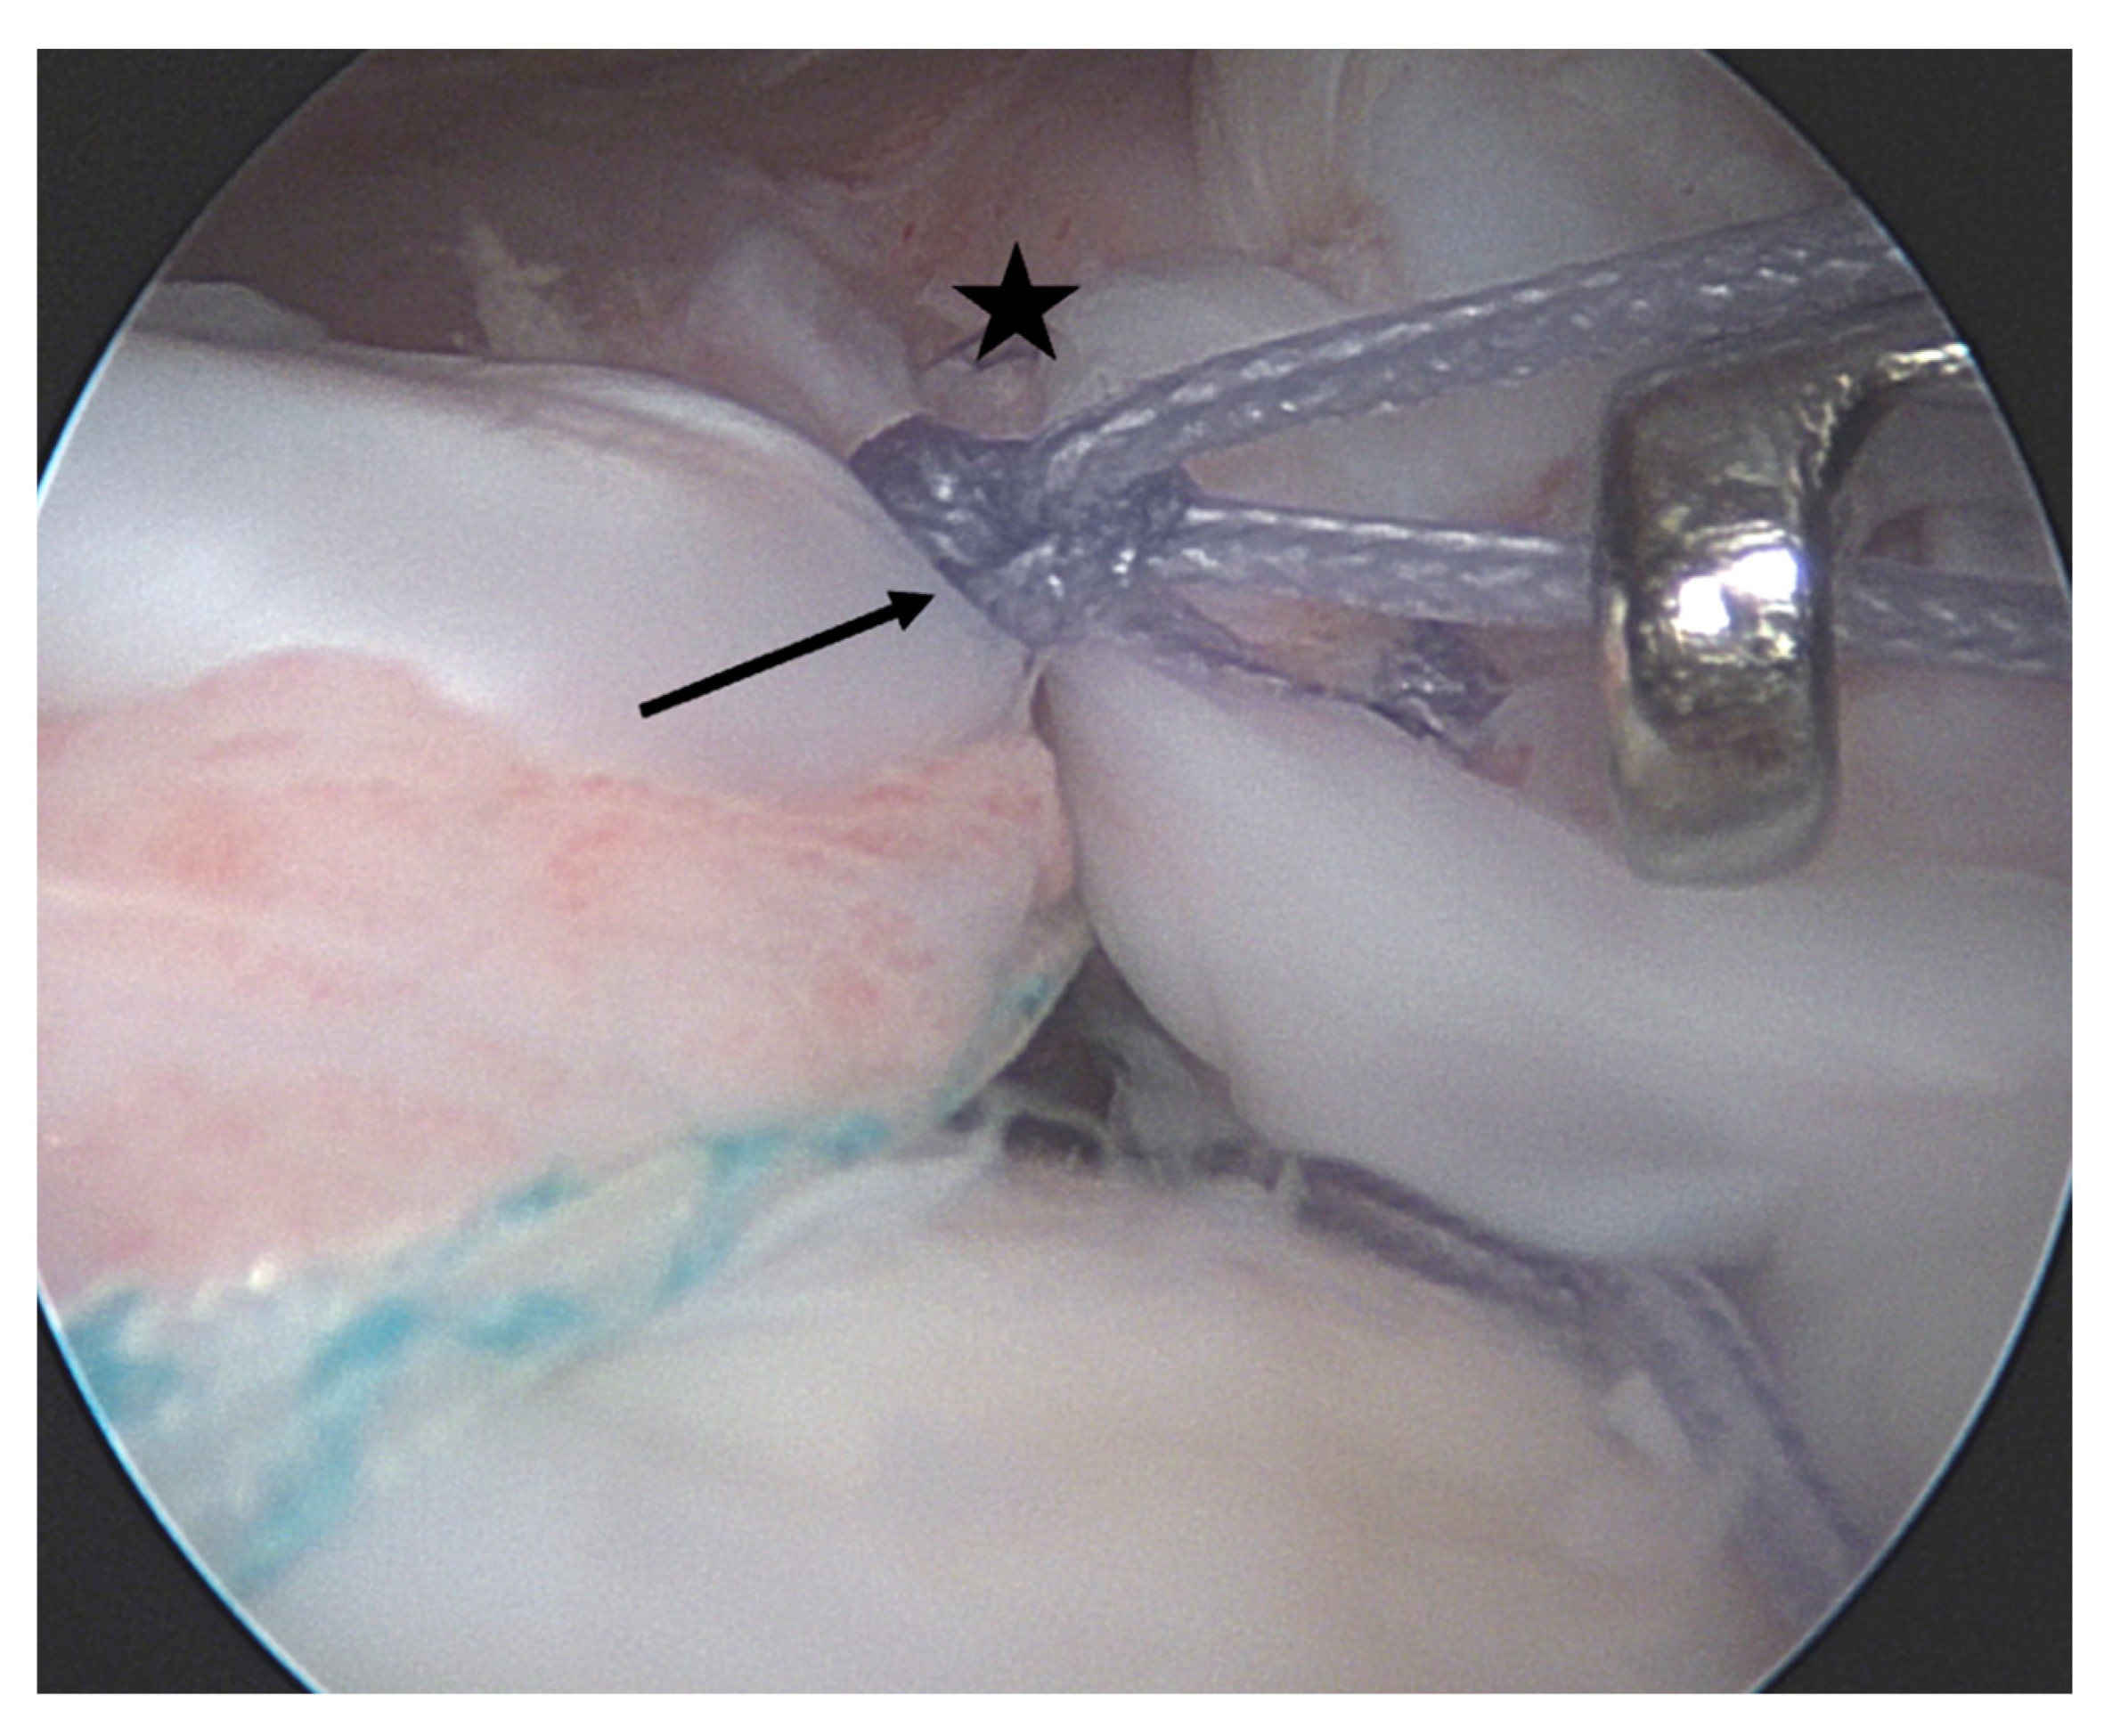

- Lo, I.K.; Burkhart, S.S. The comma sign: An arthroscopic guide to the torn subscapularis tendon. Arthrosc. J. Arthrosc. Relat. Surg. 2003, 19, 334–337. [Google Scholar] [CrossRef] [PubMed]

- Gröger, F.; Hackl, M.; Buess, E. Arthroscopic Suture-Bridge Repair of the Subscapularis Tendon—“Inside and Outside the Box” With Preservation of the Comma Sign. Arthrosc. Tech. 2021, 11, e31–e36. [Google Scholar] [CrossRef]